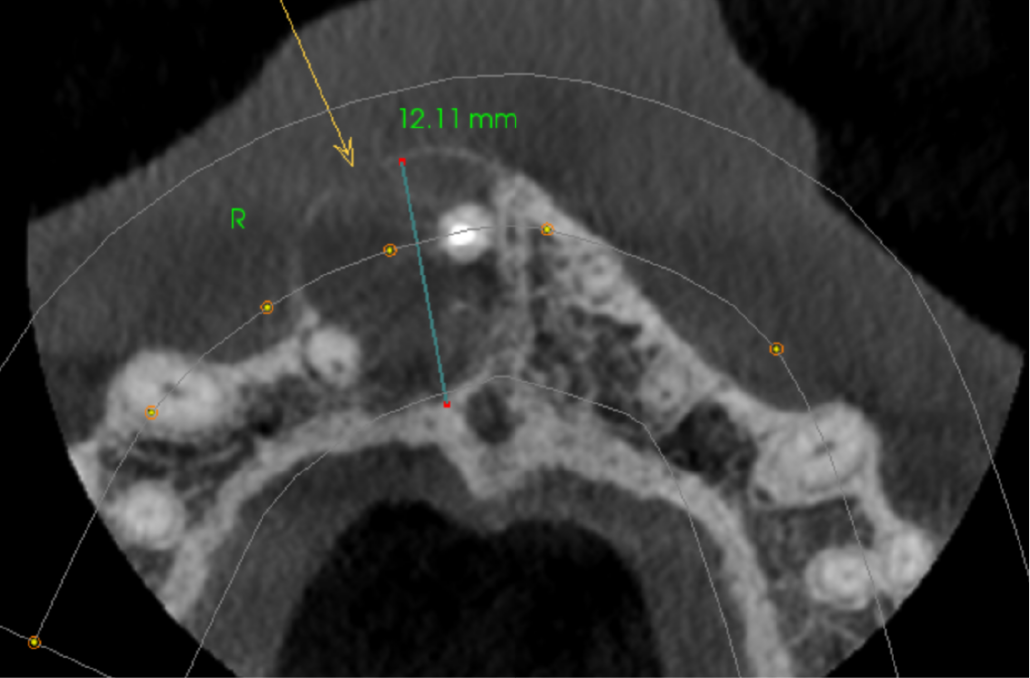

Axial view showing well defined unilocular radiolucency in UR1-UR2 area. The buccal cortex is expanded and perforated (arrow)

The UR1 is root filled with a small amount of extruded filling material inside the lesion. There is a well-defined, unilocular radiolucency measuring 12mm, extending from the UR1 apical region to the UR2 apex. The origin is probably from the apex of the UL1. The buccal cortex is expanded and perforated. The palatal cortex is eroded at the level of the oral opening of the nasopalatine canal. The lesion has not eroded the nasopalatine canal more superiorly. The appearance is that of a radicular cyst.